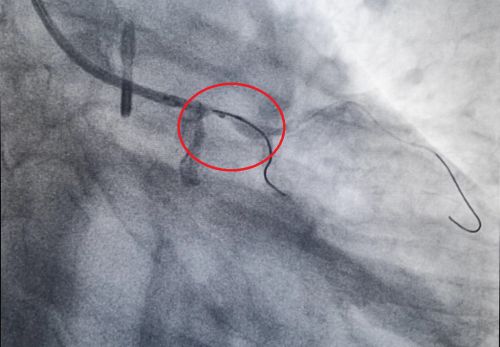

造影显示左主干狭窄95%。